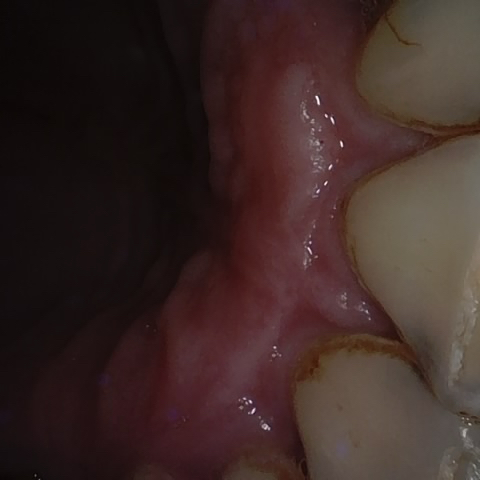

Annotated as "Good"